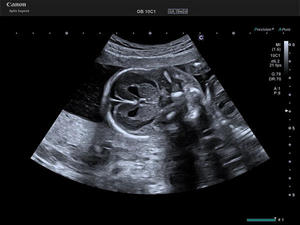

近年,女性の社会進出や生活習慣の変化に伴い,乳がんや卵巣がん,子宮筋腫などの疾患リスクが高まっている。また,晩婚化による出産年齢の高齢化により,先天性疾患や胎児発育遅延(FGR),前置胎盤などのリスクも増加している。「Aplio beyond / Women’s Healthモデル」は,これらの課題に対応するために開発された超音波診断装置。高精細な画像描出,微細な血流の観察,多彩なアプリケーションを搭載し,女性関連疾患の早期発見・診断を強力にサポートする。

Bモード画像内でRAWデータ信号の隣り合った輝度の連続性を分析し,高性能なGPU/CPUによって画像処理を行う。飽和し滲んだ箇所はシャープに表現し,信号強度が低い箇所は輝度補完を行い,バランスを整え,組織の境界および構造をシャープに描出する。さらにスペックルとして表示される実質部分は細かさを残しながら均一に,かつ実質内の細かな血管などの構造を残しながら表示して高分解能な画像を提供する。この処理を連続するフレームに対して適用することで,自然な残像感を提供し,空間の認識力を向上させた観察が期待される。

Precision Plus Fine Processing mode(PPFP)の比較イメージ

PPFP:OFF |

PPFP:ON |